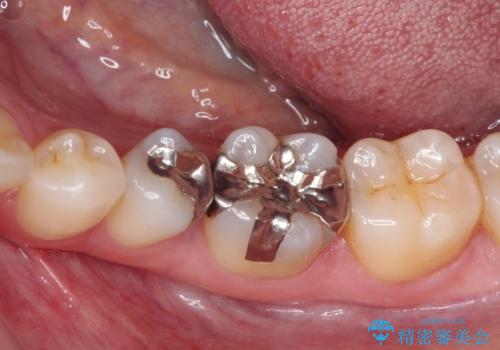

- 銀歯をセラミックにしたいとのことで来院された患者様です。

まず麻酔をして銀歯を外し、むし歯を除去し、形を整えて型取りします。

そして次の来院時、セラミックインレーを装着し、噛み合わせなどの調整を行います。

それを左右に分けて行いました。

インレーを装着するときは、唾液や血液による接着力の低下を避けるためにラバーダム防湿を行いました。